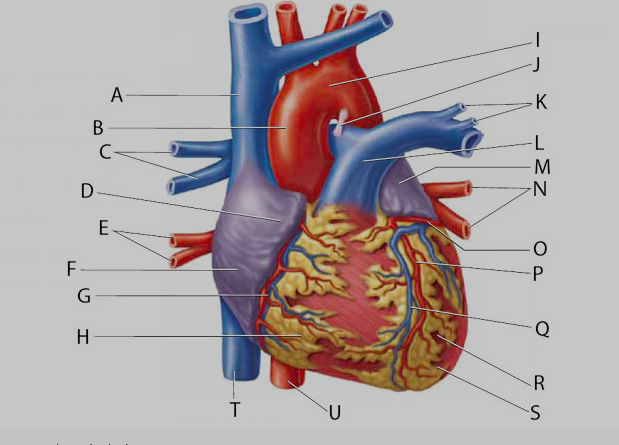

Anterior interventricular valve

Anterior interventricular sulcus

Posterior interventricular sulcus

Circumflex branch (of the left coronary artery)

Coronary sinus

Epicardium

interventricular branch of the left coronary artery. = left anterior descending artery (LADA))

Left/right atrium

Left/right auricle

Left/right coronary artery

left/right pulmonary artery/vein

left/right ventricle

Myocardium

Pulmonary trunk

Right coronary vein

Superior/inferior vena cava